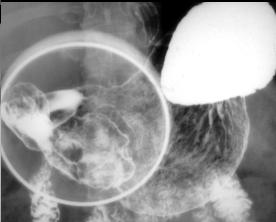

Image d'une

tumeur epitheliale de estoma . Sa taille est plus

marquee situe a la face posterieure de estomac , sa

bord est net , polylobulaire intraluminale et

hyperdense non homogene . Paroie de l;estoma reste

normale ( image TDM en coupe axiale ) |

Meme cas en coupe coronale (

frontale ) . la tumeur situe a la portion horizontal

region antral de l'estomac |